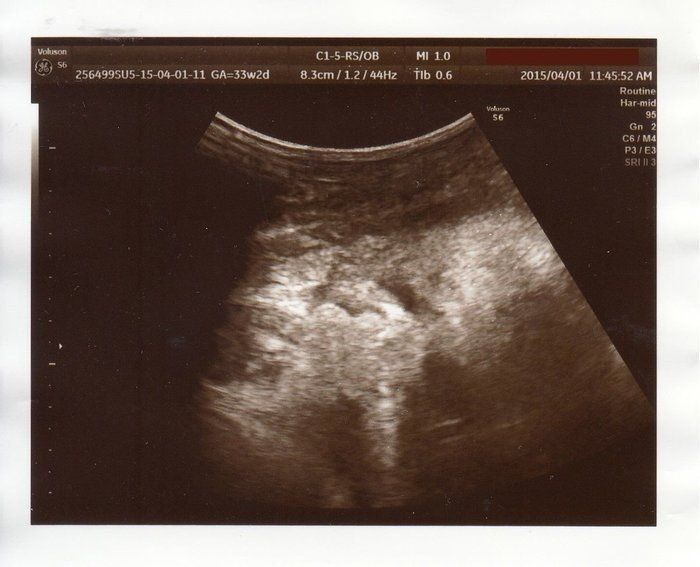

チャーミー小結さんの妊娠33週目のエコー写真

「顔上向き、黒いところは目。2200g~2300g」と記してあります。右上にある黒い丸2つが目でその間に鼻がうつっています。口を開けているところ?このころは、おなかが大きくなり自分で足の爪を切ることが難しかったので、看護師さんにお願いしていました。